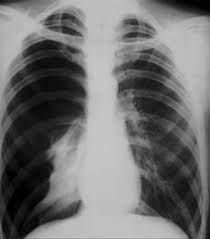

Symptoms The main symptoms of a pneumothorax are sudden chest pain and shortness of breath. Severity of symptoms may depend on how much of the lung is collapsed. When to see a doctor Symptoms of a pneumothorax can be caused by a variety of health problems, and some can be life-threatening, so seek medical attention. If your chest pain is severe or breathing becomes increasingly difficult, get immediate emergency care.